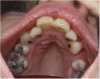

The entity described by Gunnar Stickler, which included hereditary arthro-ophthalmopathy associated with retinal detachment, has recently been recognised to consist of a number of subgroups, which might now more correctly be referred to as the Stickler syndromes. They are the most common clinical manifestation of the type II/XI collagenopathies and are the most common cause of inherited rhegmatogenous retinal detachment. This review article is intended to provide the ophthalmologist with an update on current research, subgroups, and their diagnosis together with a brief overview of allied conditions to be considered in the clinical differential diagnosis. We highlight the recently identified subgroups with a high risk of retinal detachment but with minimal or absent systemic involvement--a particularly important group for the ophthalmologist to identify.